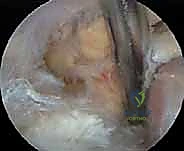

Suprascapular Notch Decompression

Once the base of the coracoid is clearly delineated, dissection proceeds medially. The conjoined tendon is identified anteriorly, and the coracoclavicular (CC) ligaments (trapezoid and conoid) are identified superiorly. The dissection follows the medial base of the coracoid process, progressing posteriorly toward the superior border of the scapula.

A Neviaser portal (superior portal) is often established at this juncture. This portal, placed in the V-shaped interval between the clavicle and the scapular spine, allows for an excellent trajectory for instrumentation perpendicular to the STSL.

Fibrofatty tissue overlying the notch is carefully cleared using a combination of blunt dissection and judicious radiofrequency ablation. The suprascapular artery is typically visualized first, running transversely superior to the STSL. The artery must be meticulously protected; inadvertent injury can lead to significant hemorrhage and retraction of the vessel into the supraclavicular fossa.

Deep and inferior to the artery lies the STSL. The ligament is probed to confirm its orientation. Using arthroscopic scissors or a narrow Kerrison punch introduced through the Neviaser or anterolateral portal, the STSL is systematically transected from medial to lateral. Complete release is confirmed by visualizing the underlying suprascapular nerve and demonstrating its free excursion within the notch.